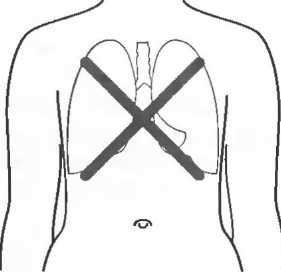

Плотные материалы, такие как кости или камни, дают акустическую тень на структуры, расположенные сзади, в результате того что ультразвуковая волна не проходит через них. Этот феномен получил название «акустической тени». Например, ребра могут экранировать ультразвуковой поток, поэтому структуры, расположенные за ними, нужно исследовать в косом направлении по межреберным промежуткам (рис. 10б,в).

Кости, камни и кальцинаты дают акустическую тень. Ультразвук не может проходить через кость, если она только не очень тонкая (как, например, кости черепа у новорожденного). При необходимости рассмотреть структуры, расположенные глубже, необходимо использовать различные углы наклона датчика (рис. 17а,б).